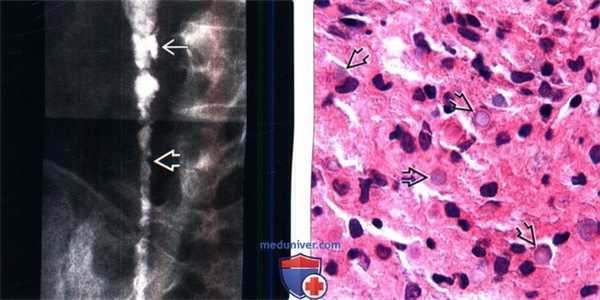

(Слева) Прицельная рентгенография правого мочеточника: у пациента с малакоплакией определяется диффузные изменения стенки мочеточника с небольшими бляшками и изъязвлениями. Поражение мочевыводящих путей может быть довольно разнообразным, от очагового образования до диффузной аномалии.

(Справа) Окрашивание гематоксилином и эозином, макроувеличение: пласты гистиоцитов (клеток фон Хансемана) с па -стинчатыми эндоплазматическими включениями (тельца Михаэлиса-Гутмана). Малакоплакия является результатом дефекта фаголизосомальной активности у пациентов с рецидивирующей инфекцией Е. coli.